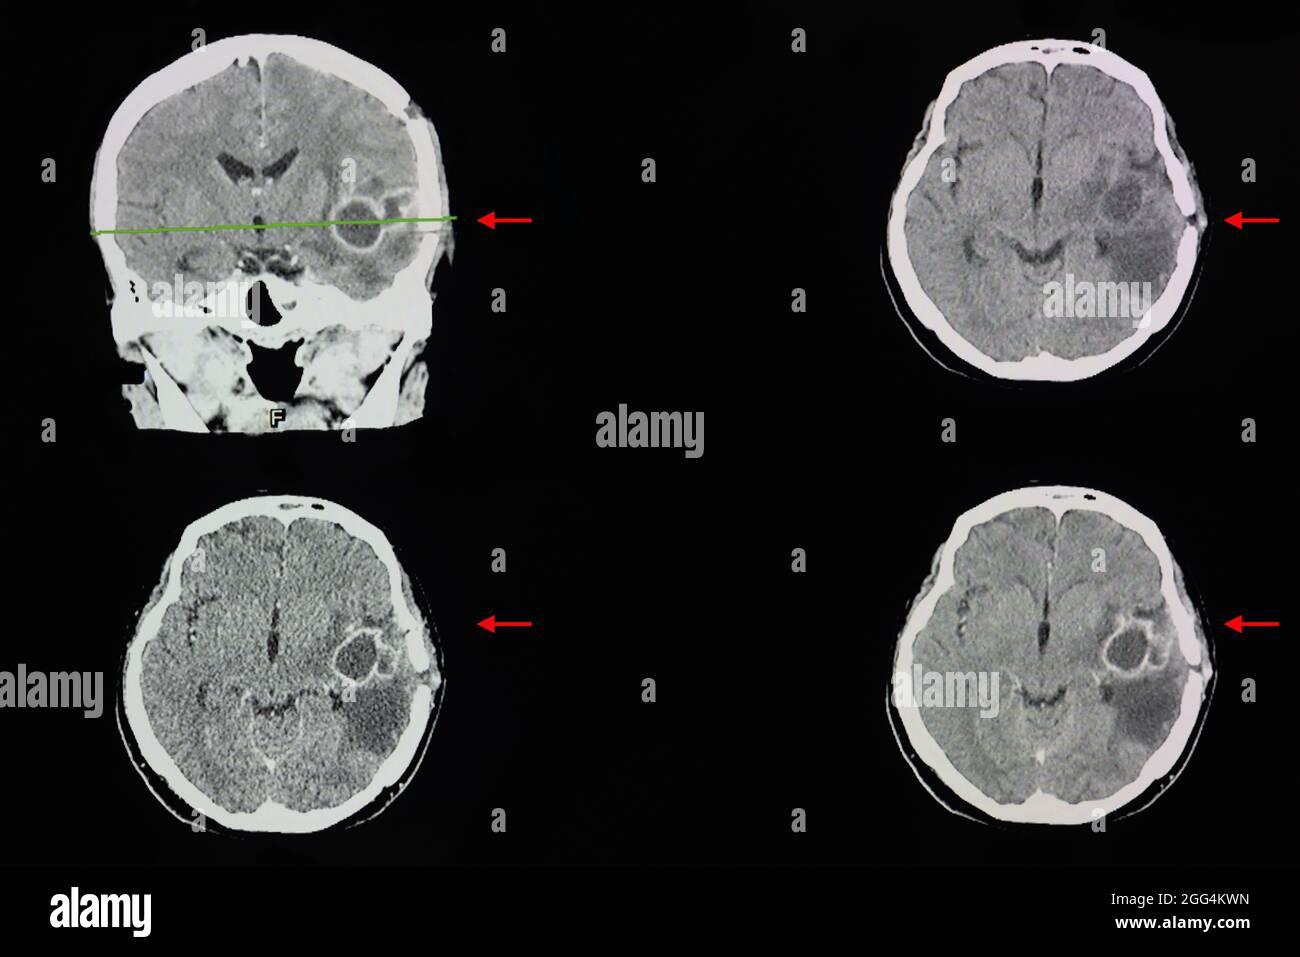

Une acquisition CT du cerveau d'un patient présentant de grands abcès cérébraux dans son lobe temporal gauche. Banque D'Imageshttps://www.alamyimages.fr/image-license-details/?v=1https://www.alamyimages.fr/une-acquisition-ct-du-cerveau-d-un-patient-presentant-de-grands-abces-cerebraux-dans-son-lobe-temporal-gauche-image440197102.html

Une acquisition CT du cerveau d'un patient présentant de grands abcès cérébraux dans son lobe temporal gauche. Banque D'Imageshttps://www.alamyimages.fr/image-license-details/?v=1https://www.alamyimages.fr/une-acquisition-ct-du-cerveau-d-un-patient-presentant-de-grands-abces-cerebraux-dans-son-lobe-temporal-gauche-image440197102.htmlRF2GG4KW2–Une acquisition CT du cerveau d'un patient présentant de grands abcès cérébraux dans son lobe temporal gauche.

TDM cérébrale avec contraste d'un patient présentant une lésion rehaussant le bord de 3.8 cm au niveau du sinus caverneux droit avec calcification interne, le plus probable ménigiome Banque D'Imageshttps://www.alamyimages.fr/image-license-details/?v=1https://www.alamyimages.fr/tdm-cerebrale-avec-contraste-d-un-patient-presentant-une-lesion-rehaussant-le-bord-de-3-8-cm-au-niveau-du-sinus-caverneux-droit-avec-calcification-interne-le-plus-probable-menigiome-image440197160.html

TDM cérébrale avec contraste d'un patient présentant une lésion rehaussant le bord de 3.8 cm au niveau du sinus caverneux droit avec calcification interne, le plus probable ménigiome Banque D'Imageshttps://www.alamyimages.fr/image-license-details/?v=1https://www.alamyimages.fr/tdm-cerebrale-avec-contraste-d-un-patient-presentant-une-lesion-rehaussant-le-bord-de-3-8-cm-au-niveau-du-sinus-caverneux-droit-avec-calcification-interne-le-plus-probable-menigiome-image440197160.htmlRF2GG4KY4–TDM cérébrale avec contraste d'un patient présentant une lésion rehaussant le bord de 3.8 cm au niveau du sinus caverneux droit avec calcification interne, le plus probable ménigiome